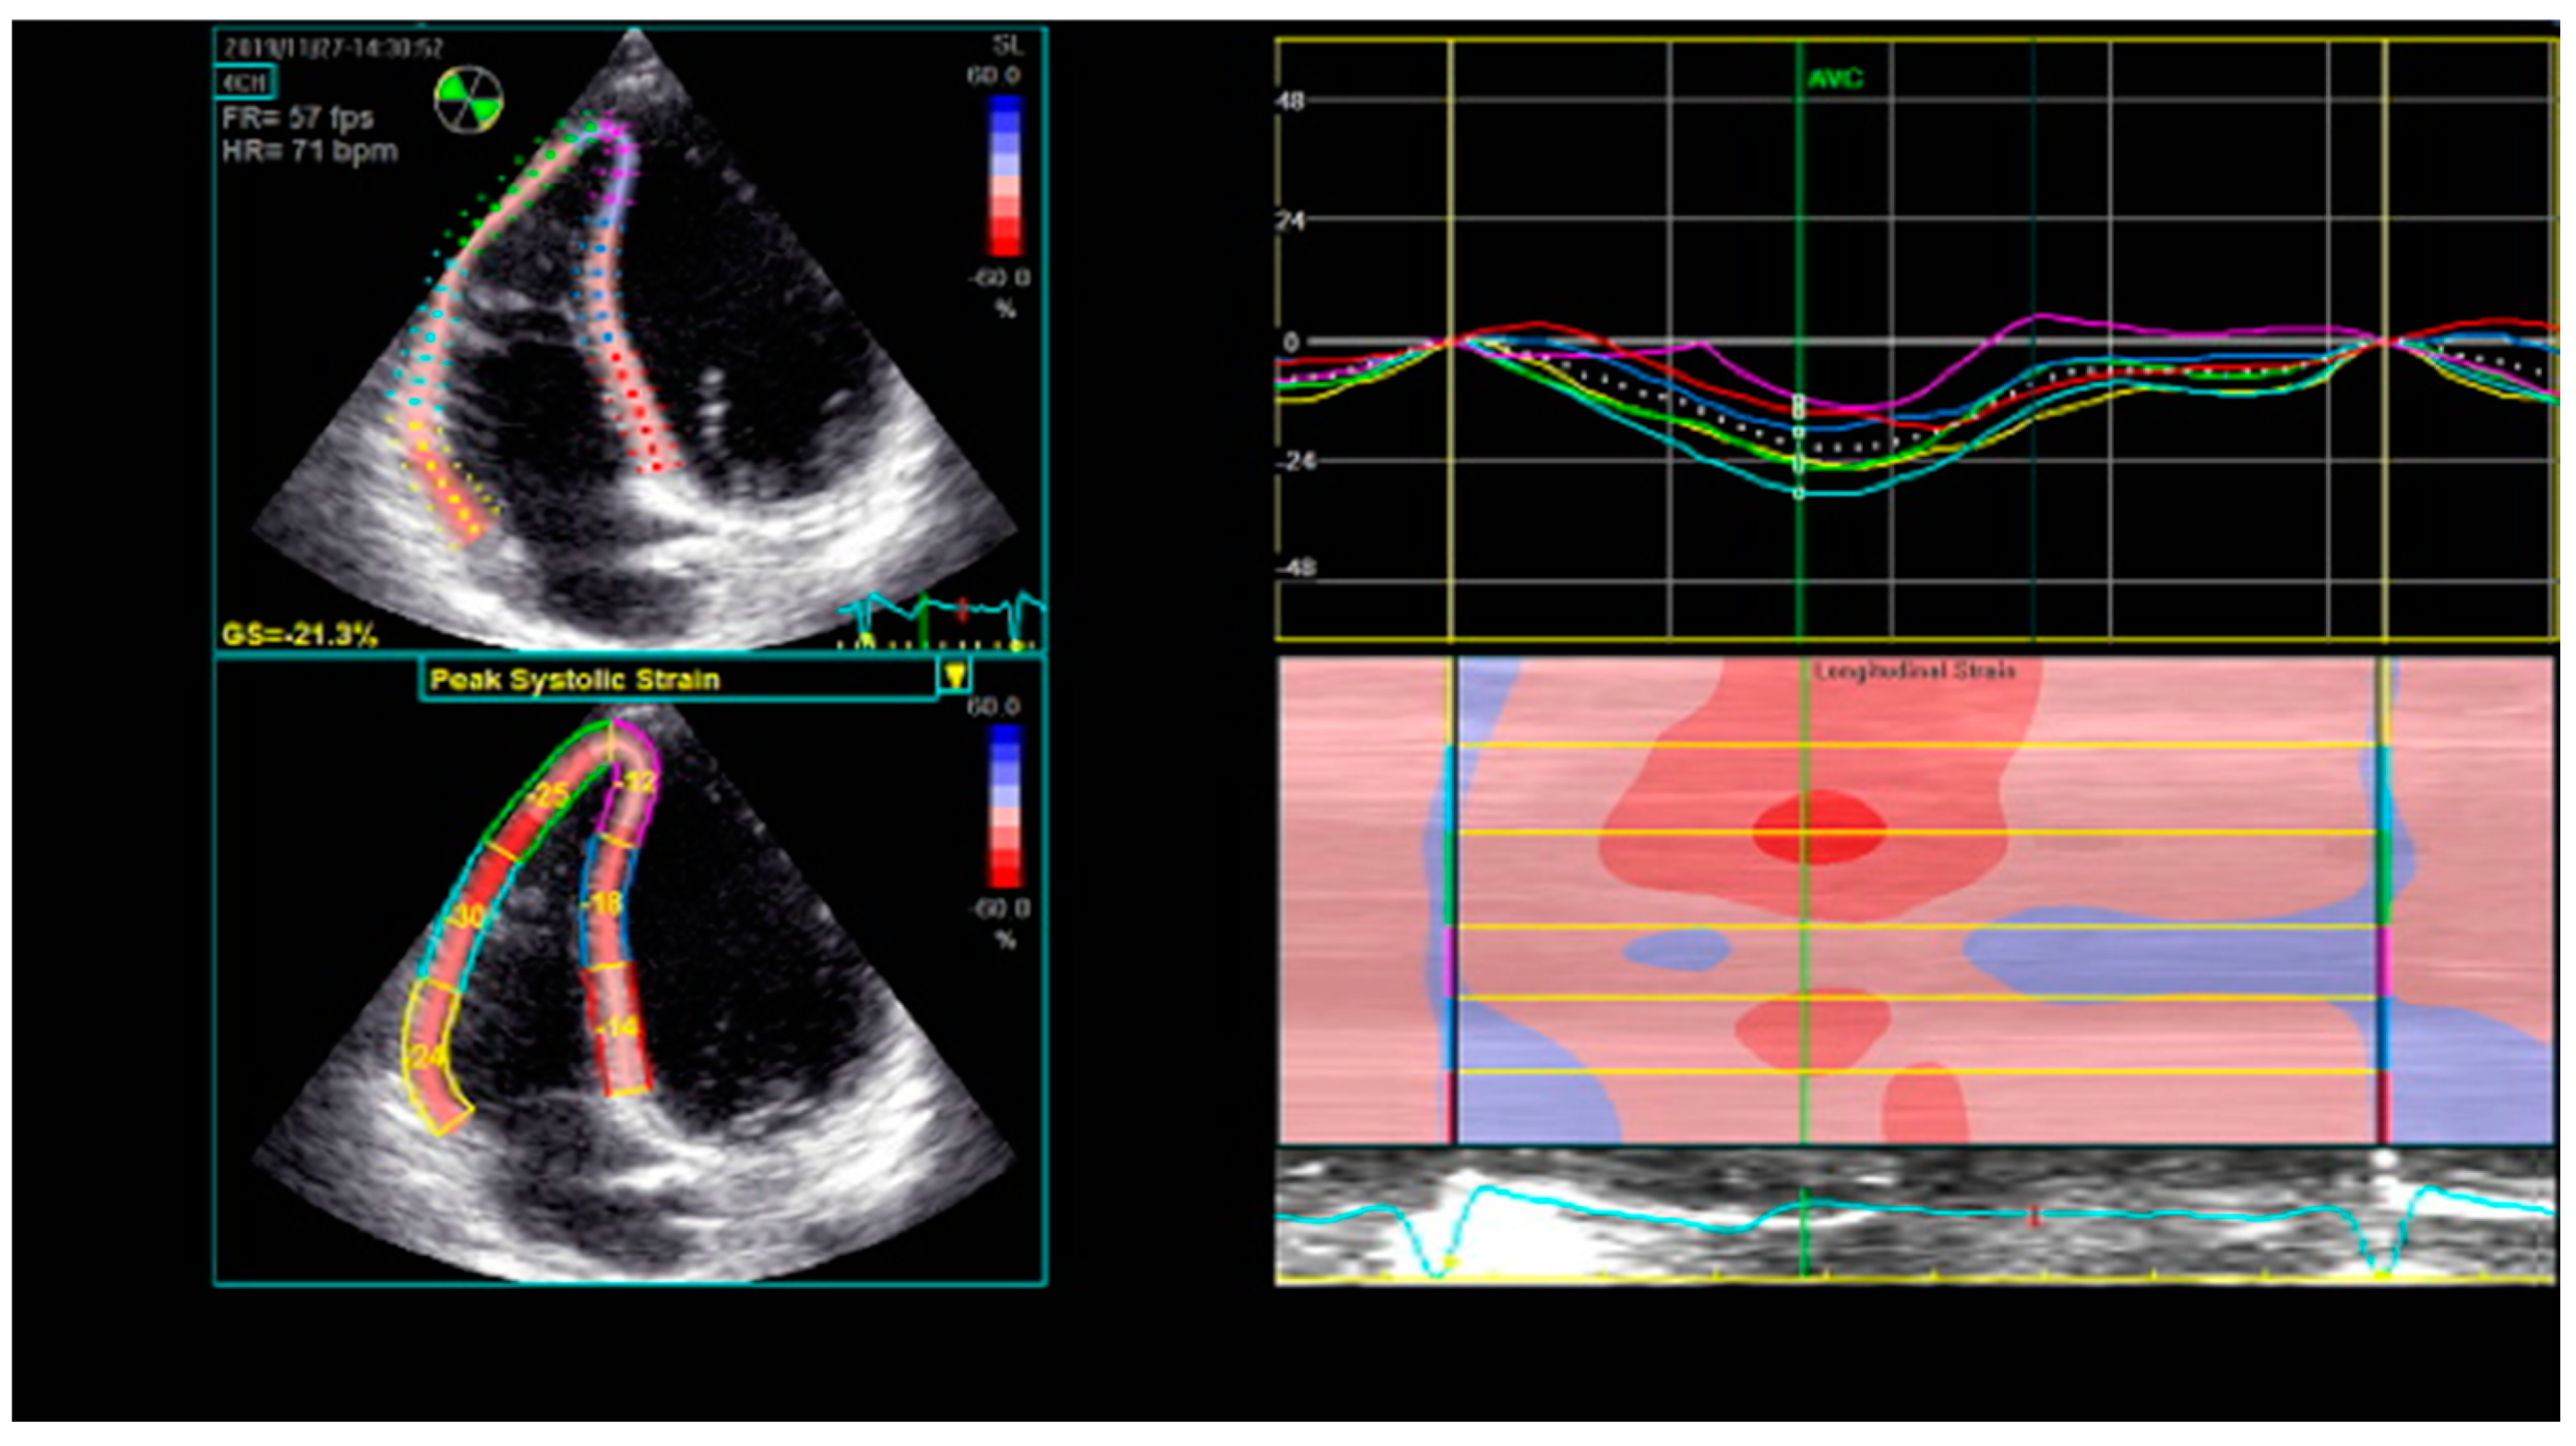

Speckle-tracking echocardiography is a non-invasive, innovative technique that analyzes the segmental myocardial deformation along different planes through the displacement of speckles [25]. Originally designed for the assessment of the LV, it is now also being applied for the analysis of RV deformation. Strain represents the percentage change in length of a myocardial segment, while strain rate represents the rate of deformation over time [56]. Both strain and strain rate are indices of myocardial contractility [57]. The RV longitudinal strain and strain rate may be measured in the apical RV-focused four-chamber view, using the software dedicated for the LV assessment. The RV free wall and the interventricular septum (IVS) are each divided into three segments (basal, medial, and apical), providing a six-segment model (Figure 3). The global longitudinal strain of the RV is calculated as the average of the six segmental values, while the longitudinal strain of the RV free wall (RVFW) is calculated as the average of the three segmental values of the free wall [58]. The latter is considered to be more specific for the RV [25], since the motion of the IVS contributes to both RV and LV function.

Figure 3.

Six-segment model of longitudinal RV strain using STE. RV—right ventricle; STE—speckle-tracking echocardiography.

STE assesses the deformation of myocardial speckles in two dimensions along the myocardial wall direction, thus being less confounded by the motion of the heart [59] and relatively angle-independent when compared to TDI-derived parameters [60]. The advantages of 2D-STE-derived strain are the angle independence, the relative load independence, the strong correlation with RVEF measured by CMR [61], and the ability of detecting subtle myocardial abnormalities, which cannot be identified using conventional parameters [62,63]. One study showed that RVFW strain had a good correlation with the extent of myocardial fibrosis detected on CMR [64]. However, there is no uniformity among software and no reference range agreement between vendors. Other drawbacks are that strain assessment is dependent on good image quality, it is influenced by artifacts, and it neglects the contribution of the RV outflow tract (RVOT) to the global RV performance [26]. For the longitudinal strain of the RV free wall, a value > −20% is considered abnormal [26].